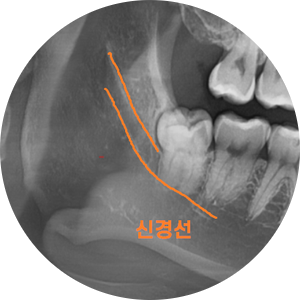

이렇게 누워있는 사랑니는 딱봐도 뽑기 어렵게 생겼죠?

그냥 잡고 뽑으면 방향이 가로라

나올 수가 없어요~

이런 치아는 쪼개서 조각을 내어 뽑아줘야합니다.

시간이 많이 걸리겠죠~?

매복 사랑니의 경우 신경관과 근접한 경우가 많아

ct까지 같이 찍게 되는데요~